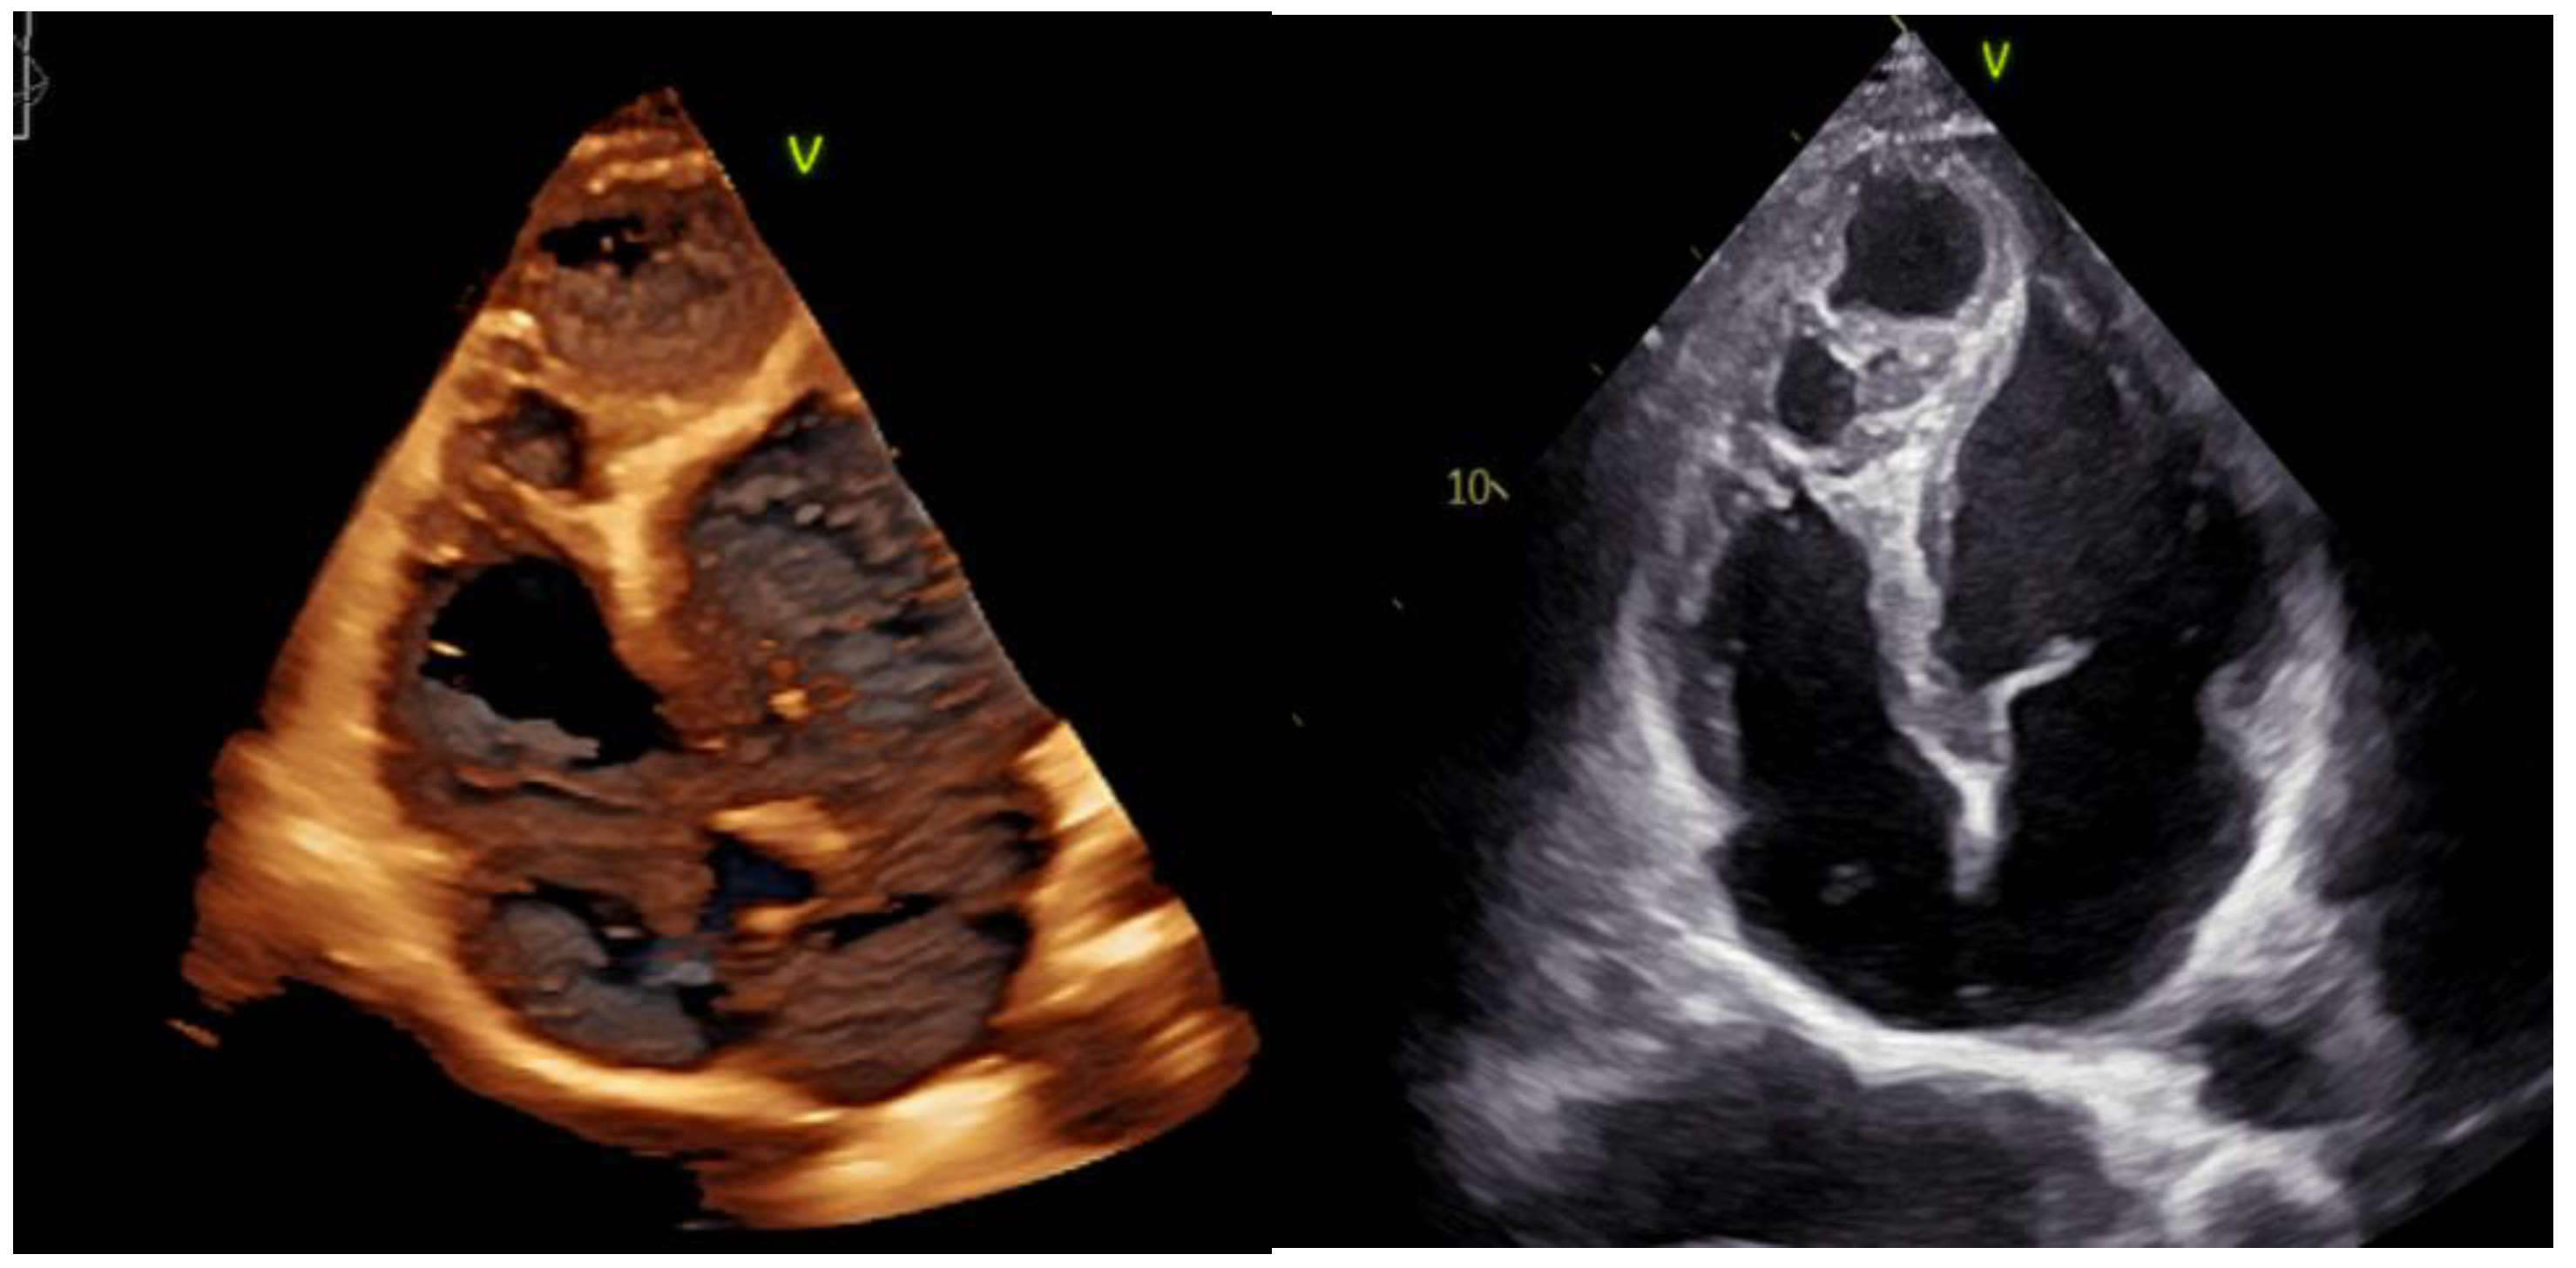

2. Case Presentation